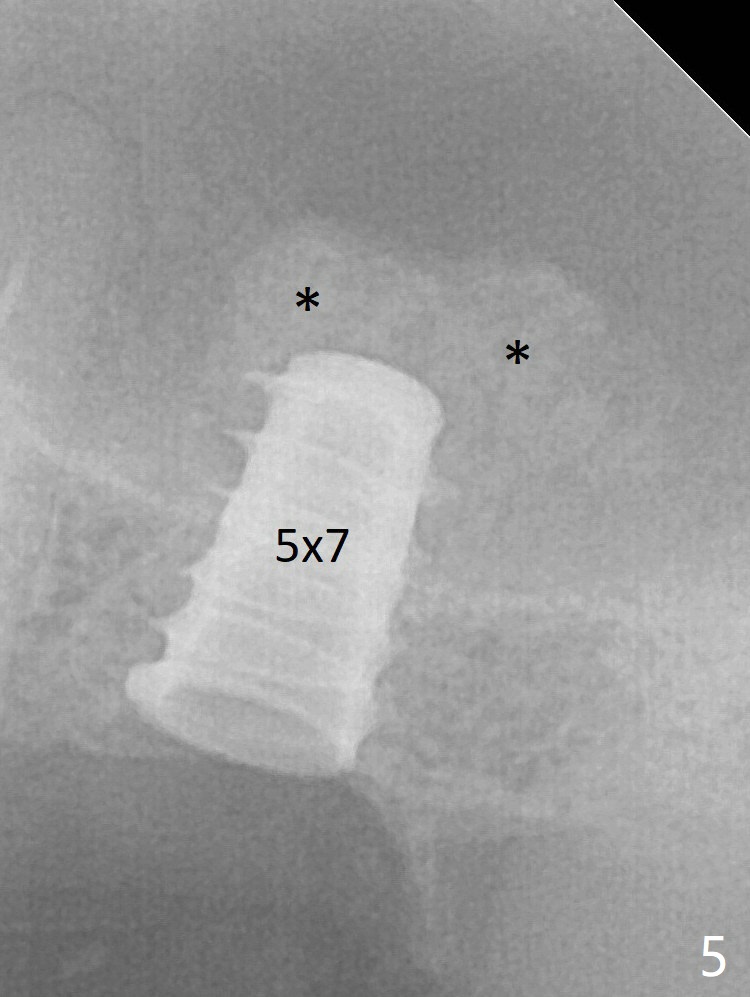

Following minimal use of Magic Lifter, Vanilla Graft is inserted (Fig.4 *) and a 4x9 mm dummy implant is placed partially.  It appears that the implant is a little too long.  After placement of more allograft (Fig.5 *), a 5x7 mm implant is placed with ~ 35 Ncm.  With placement of a 5.5x4(2) mm abutment, an immediate provisional is fabricated to close the socket.  Six months postop, the bone graft remains in the sinus around the apical end of the implant (Fig.6 *), while there seems no bone loss coronally (Fig.7).